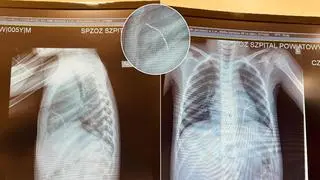

- Kawałek drutu przeszedł idealnie między żebrami, przeszedł przez śródpiersie i wbił się w lewą komorę serca, zatrzymując się na przeponie - opowiada dr Marek Kopala, kierownik kliniki kardiochirurgii w "Matce Polce".

Rodziców zaalarmowało to, że po pewnym czasie dziecko zaczęło sinieć i słabnąć. Pięciolatek został przewieziony karetką do szpitala w Opocznie, gdzie wykonano zdjęcie rentgenowskie. A na nim - jak opowiadał w rozmowie z tvn24.pl pełniący wtedy obowiązki lekarz Paweł Banaszek - długi na kilka centymetrów cień metaliczny w sercu. Chłopczyk został stamtąd śmigłowcem przetransportowany do "Matki Polki" w Łodzi. Szybka diagnoza być może uratowała życie dziecka.

Drut wbił się w lewą komorę serca chłopca